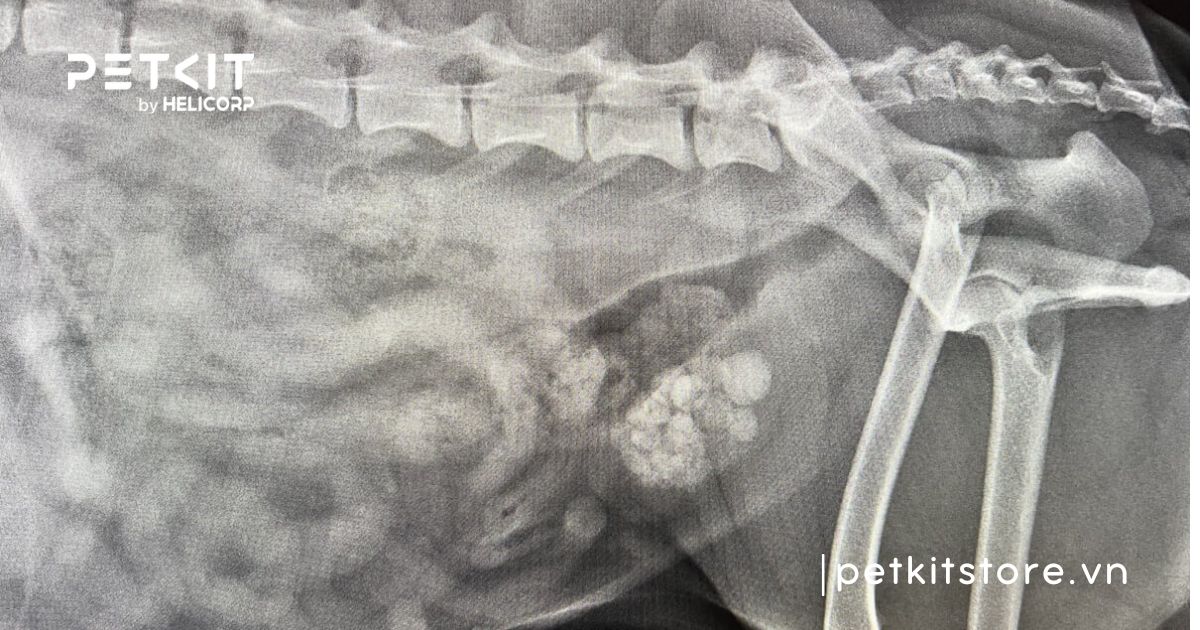

Chụp X-quang/Siêu âm bàng quang: Hầu hết các loại sỏi bàng quang đều có thể nhìn thấy qua X-quang hoặc siêu âm. Các kỹ thuật chẩn đoán hình ảnh này sẽ được thực hiện trên những bé mèo có dấu hiệu đau bụng, tiểu ra máu hoặc rặn tiểu nhiều lần, giúp xác định chính xác vị trí và kích thước của sỏi.

Chụp X-quang để phát hiện sỏi bàng quang ở mèo